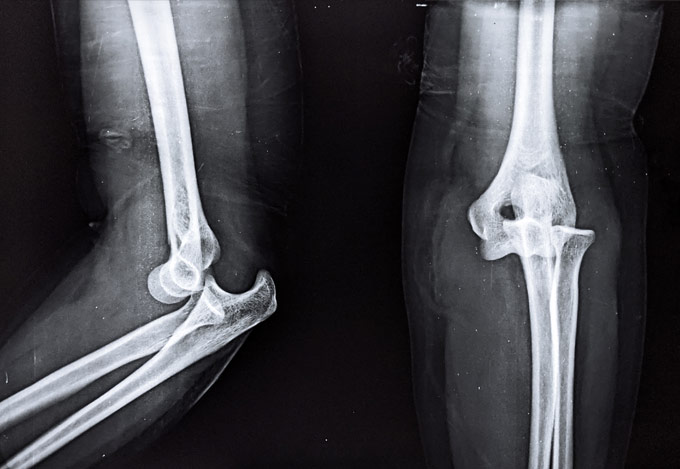

Έχει 5ετή μετεκπαίδευση και εργασία στο Ηνωμένο Βασίλειο ως ειδικός Ορθοπαιδικός Χειρουργός. Έχει εργαστεί στα Ορθοπαιδικά Τμήματα των Νοσοκομείων Southampton University Hospitals NHS Trust, Leeds Teaching Hospitals NHS Trust και στο Northampton General Hospital NHS Trust, με υποεξειδίκευση στη Χειρουργική Ώμου, Γόνατος, Ισχίου, Ποδοκνημικής & Άκρου Ποδός, Ώμου & Αγκώνος και Γενικού Τραύματος Ενηλίκων και Παίδων.